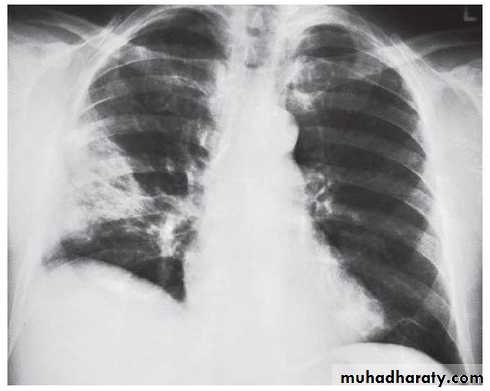

Nodular (coin) lesion in the left upper lung with irregular edge (most probably cancinoma